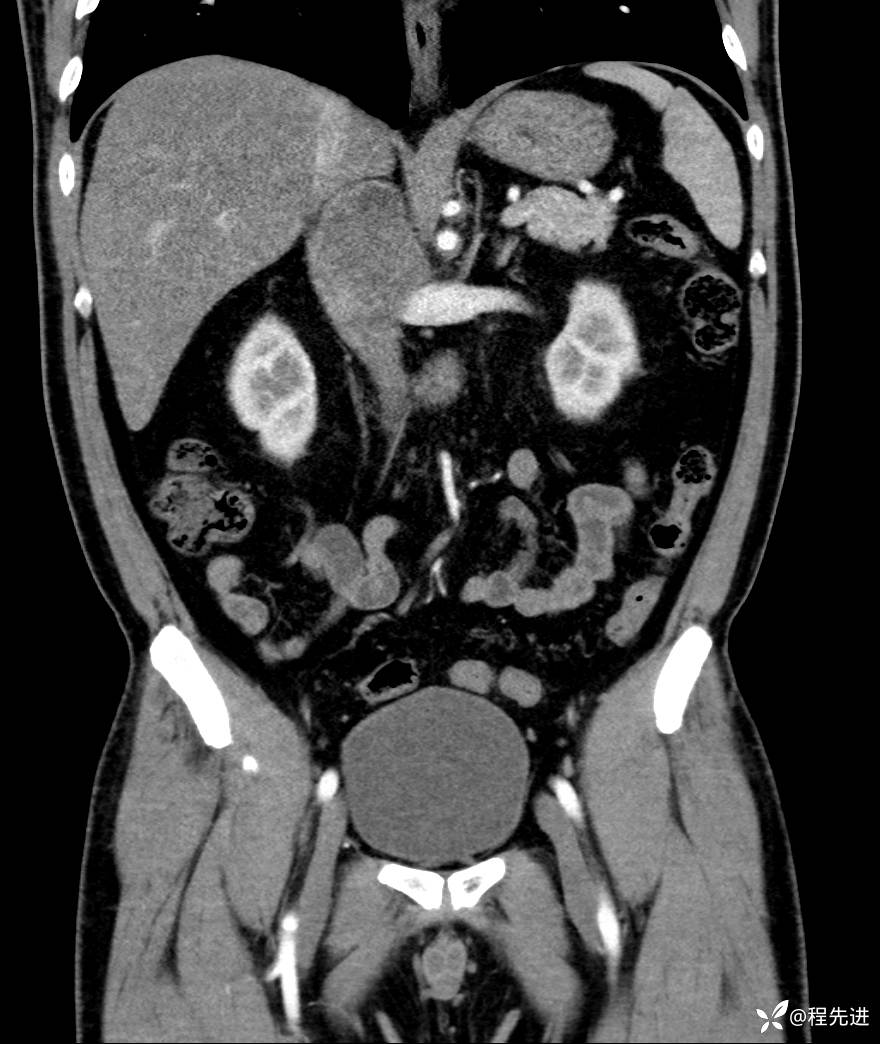

【腹盆】特别精彩病例|发现腹膜后肿物1月余

主诉:发现腹膜后肿物1月余

现病史:患者1月余前查体,行超声检查提示:后腹膜囊实性肿块;慢性胆囊炎伴胆囊内结石;无腹痛腹胀,不伴腹泻发热等;偶感腰背部酸痛。

实验室检查:乙肝表面抗原(+),乙肝e抗体(+),乙肝核心抗体(+)

CT平扫+增强: